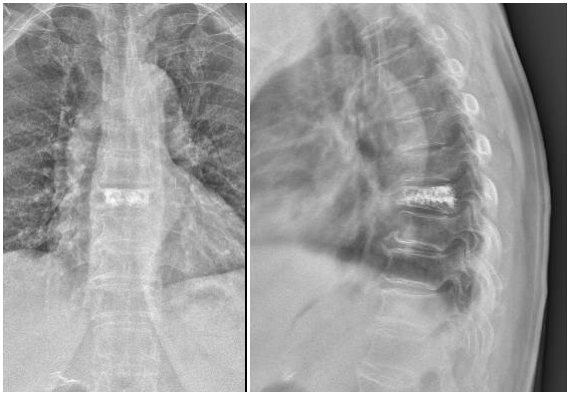

明確診斷后,太原市中心醫院骨科汾東一病區脊柱微創組團隊為患者實施了椎體成形術。術后,患者疼痛明顯減輕,并可下地行走。

骨折壓縮明顯,疼痛癥狀嚴重,可以采用手術治療。目前,椎體成形術已被廣泛用于臨床并取得很好的效果。椎體成形術是在影像指導下,將穿刺針經皮穿刺到病變椎體后,向椎體內注入骨水泥,既可以消除或緩解疼痛癥狀,又能加固和強化椎體從而防止進一步塌陷。